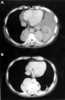

Multiple pleural masses

Mesothelioma